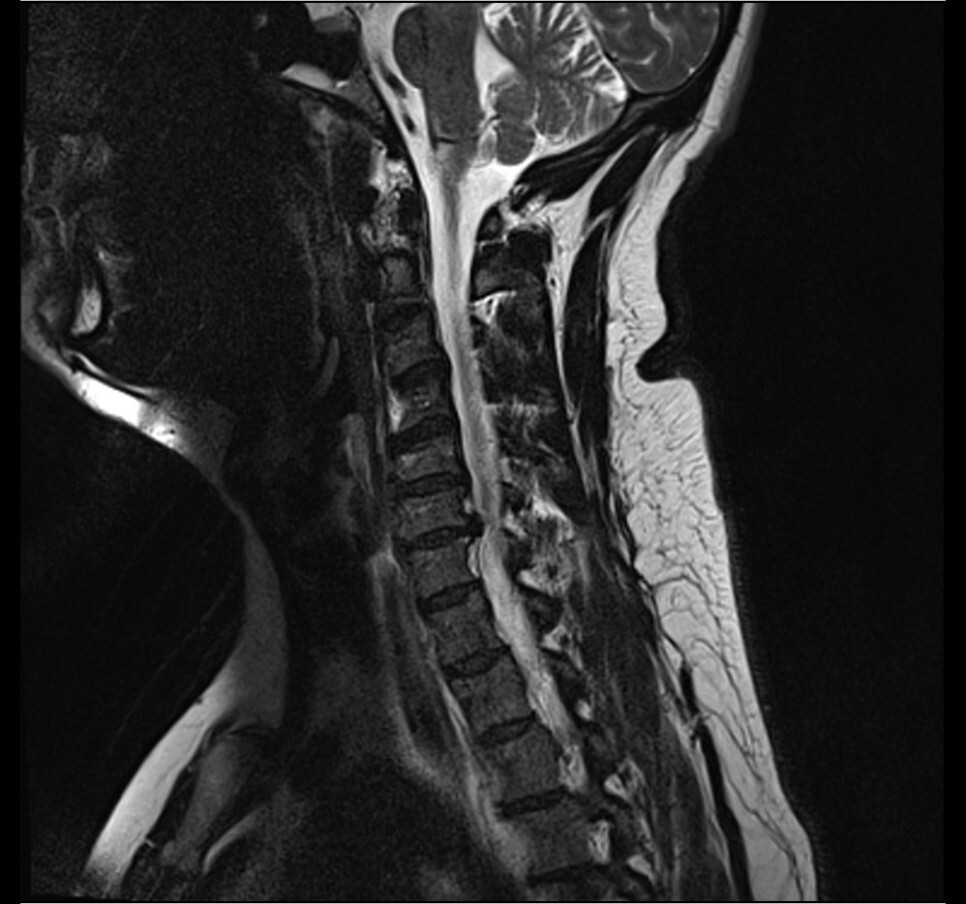

소위 목 디스크라 부르는 경추 추간판 탈출증 환자가 점차 늘어나고 있습니다. 대개 진단 시 영상의학적 소견에만 의지하다 보니 기본적인 근력 저항 검사조차 시행하지 않는 경우가 흔해집니다. 그래도 일차진료의라면 기본적인 검사는 시행해야겠죠.